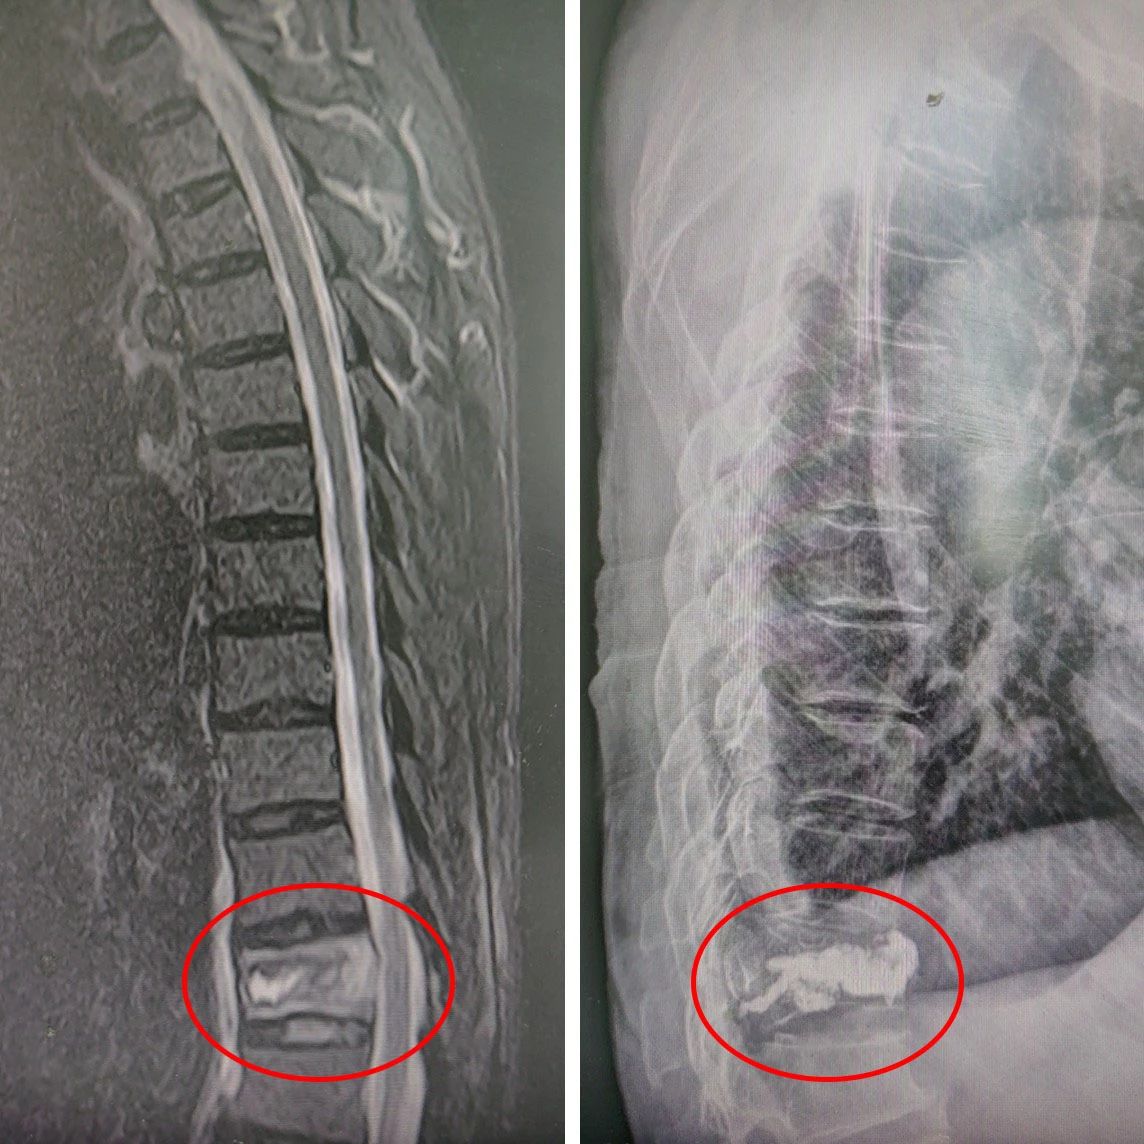

△ 术前:磁共振明确骨折 △ 术后:“骨水泥”已“就位”

数日前,吴先生(化名)在家中不慎摔倒,腰部遭受严重疼痛。在当地医院接受核磁共振检查后,发现第12胸椎出现骨折。巧的是,吴先生的妻子此前也曾遭遇胸腰椎骨折,并在我院由骨伤科华国军主任主刀进行手术治疗,术后恢复情况令患者十分满意。考虑到这次吴先生再次面临类似的骨伤问题,家里人一合计,决定将他从南通如皋老家连夜送至我院接受治疗。吴先生于17日晚上11点多抵达医院,并顺利办理了住院手续。经过对吴先生的身体状况进行全面评估,华国军主任决定采用经皮穿刺椎体后凸成形术(PKP)为其进行治疗。

经皮穿刺椎体后凸成形术(PKP),简单来说,就是像“打针”一样,用一个直径约5毫米的针,直接穿刺到骨折部位,先用球囊扩张使椎体复位,然后注入一种叫“骨水泥”的药物,从而稳定骨折、恢复椎体强度、防止椎体进一步压缩和缓解疼痛,能够帮助病人尽快恢复正常活动。